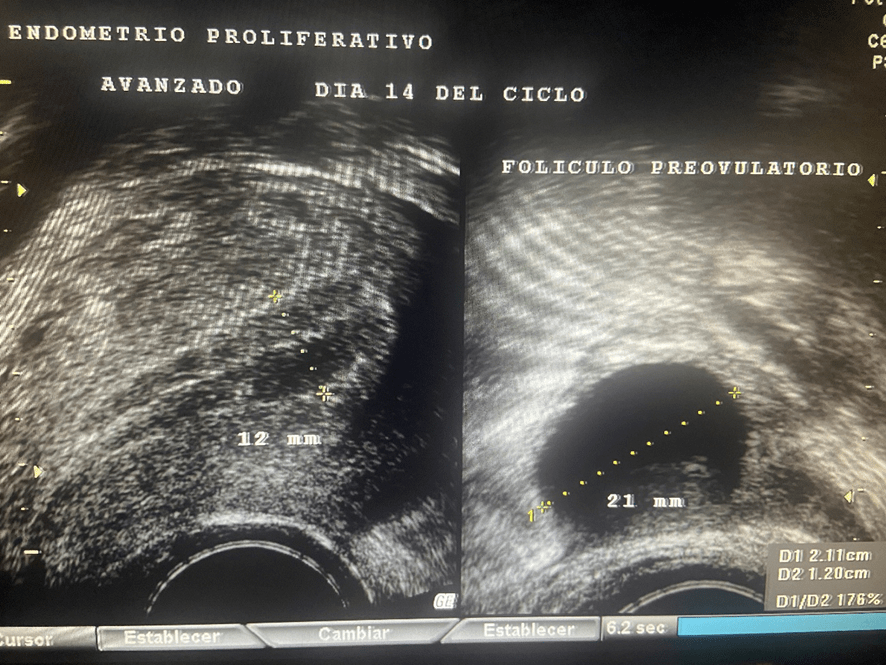

Además de estrógenos, este cuerpo lúteo empieza a segregar una hormona llamada Progesterona; la cual, es la causante de que el endometrio- que antes de la ovulación era proliferativo y con sus tres capas bien definidas- se transforme en un endometrio grueso, espeso e irregular. Se le conoce como “endometrio secretor”.

Sumando los 14 días que suele durar la fase folicular o proliferativa a los otros 14 que dura la fase lútea, luteínica o secretora, nos dan los 28 días que suele durar el ciclo menstrual.